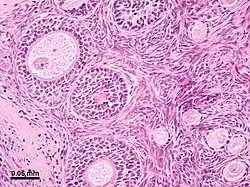

Micrograph of the ovarian cortex from a rhesus monkey showing several round follicles embedded in a matrix of stromal cells. A secondary follicle sectioned through the nucleus of an oocyte is at the upper left, and earlier stage follicles are at the lower right. The tissue was stained with the dyes hematoxylin and eosin.

The outer layer is the ovarian cortex, consisting of ovarian follicles and stroma in between them. Included in the follicles are the cumulus oophorus, membrana granulosa (and the granulosa cells inside it), corona radiata, zona pellucida, and primary oocyte. Theca of follicle, antrum and liquor folliculi are also contained in the follicle. Also in the cortex is the corpus luteum derived from the follicles. The innermost layer is the ovarian medulla.[8] It can be hard to distinguish between the cortex and medulla, but follicles are usually not found in the medulla.

Follicular cells are flat epithelial cells that originate from surface epithelium covering the ovary. They are surrounded by granulosa cells that have changed from flat to cuboidal and proliferated to produce a stratified epithelium.